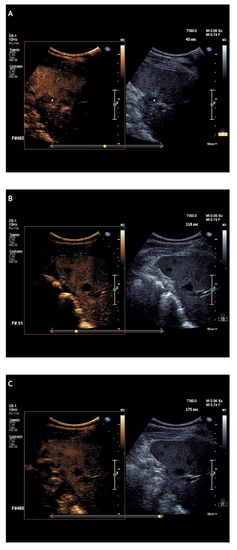

2.2.2. Splenic CEUS Patterns

2.2.3. Splenic CEUS Test Positivity

| Sarcoidosis, n = 20 | 1.5 (0.5–2.2) | Globally, hypoechoic compared to the surrounding parenchyma | Globally, hypoechoic (without later washout) compared to the surrounding parenchyma | Lymph nodes biopsy plus imaging follow-up after treatment, n = 20 |

| Hemangiomas, n = 20 | 1.5 (1.1–6) | Isoenhancement (n = 10), capillary hemangiomas Discontinuous globular peripheral enhancement (n = 10), cavernous hemangiomas | With or without later washout of mild degree as intensity (n = 10), capillary hemangiomas Progressive centripetal fill-in or very late (>3 min) washout of mild degree (n = 10), cavernous hemangiomas | Clinical and imaging follow-up, n = 20 |

| Abscesses, n = 10 | 1.1 (0.7–1.5) | Thin rim hyperenhancement pattern | Washout | Blood culture, n = 10 (positive test for fungus, n = 8; positive test for bacteria, n = 2) plus imaging monitoring after anti-microbial therapy |

| G-CSF-related myeloid metaplasia, n = 4 | 2.5 (2–3.2) | Relative hypoenhancement of the periphery of nodule and normal enhancement in the remaining portion of lesion compared to the surrounding parenchyma (reversed rim-enhancement) | Isoenhancement | Clinical and imaging follow-up, n = 4 |